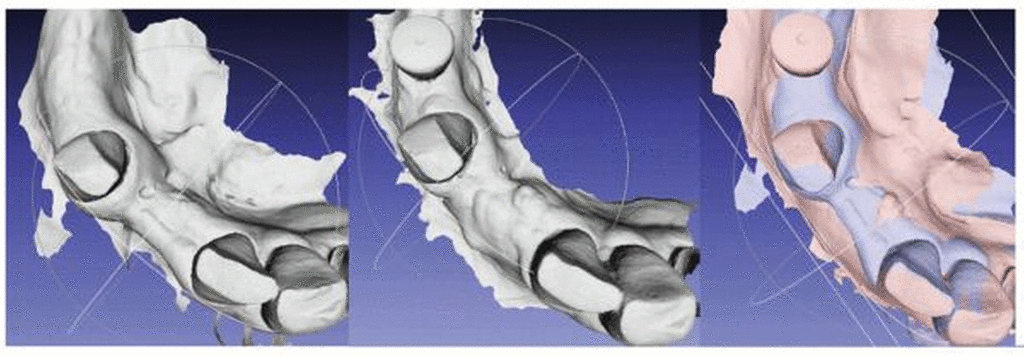

Obwohl eine Überlagerung der Zahnhartgewebe von DVT und Intraoralscan/Modellscan zunächst trivial klingt, kann dieser Schritt durchaus fehlerbehaftet sein. Wird im Sinne eines Dosis-sparenden Ansatzes ein kleines FOV gewählt, kann es passieren, dass das Matching inakkurat ist. Dies ist in Abbildung 6 dargestellt: Im linken Bild (6a) wurde ein Modellscan mit einem DVT überlagert und ein zufriedenstellendes Ergebnis erzielt. Betrachtet man jedoch das rechte Bild (6b) mit einem größeren FOV und der Überlagerung aus Abbildung 6a, so erkennt man plötzlich den Rotationsfehler. Hätte man eine Schablone zur Implantatinsertion anhand der Überlagerung aus 6a geplant, ließe sich diese nicht in der vorgesehenen Position im Mund einsetzen (da sie im dritten Quadranten innerhalb der Zahnhartsubstanz verlaufen würde). Würde man die Schablone in der „passenden“ Position auf den Zähnen einsetzen, würde sie im dritten Quadranten nicht mehr in der zuvor geplanten Position sitzen. Folglich würden ein Versatz und ein Winkelfehler bei der Implantat-Insertion resultieren.

Aus diesem Grund ist es essenziell, die Güte einer Registrierung von digitalem Modell und DVT zu prüfen, bevor Insertionsschablonen erstellt werden. Fehlerhafte Registrierungen können auch auftreten, wenn Metallrestaurationen im Patientenmund vorhanden sind und es dadurch zu Artefakten im DVT kommt. Flügge et al. konnten darlegen, dass in solch einem Fall durch eine manuelle Segmentierung des Knochens und der Zähne der Matchingfehler deutlich reduziert werden kann [Flügge et al., 2017].